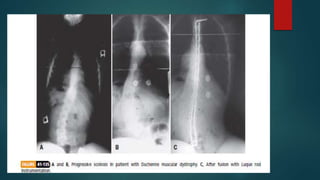

 3)Neuromuscular

a)neuropathic

b)Myopathic

1)progressive(e,g. muscular dystrophy)

2)Static(e,g. Amyotonia congenita)

NEUROMUSCULAR SCOLIOSIS

 The specific causes of neuromuscular scoliosis are unknown, but several

contributing factors are well known.

 Loss of muscle strength or voluntary muscle control and loss of sensory

abilities, such as proprioception, in the flexible and rapidly growing spinal

column of a juvenile patient are believed to be factors in development of these

curves.

 Neuromuscular curves develop at a younger age than do idiopathic curves, and

a larger percentage of neuromuscular curves are progressive.

 Unlike idiopathic curves, even small neuromuscular curves may continue to

progress beyond skeletal maturity.

 Many neuromuscular curves are long, C-shaped curves that include the sacrum,

and pelvic obliquity is common.